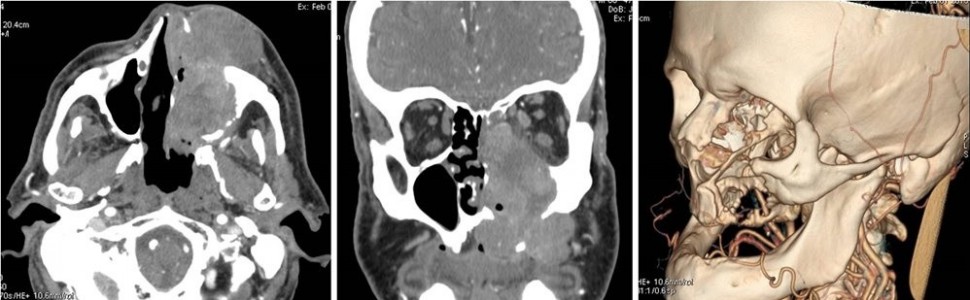

Diagnostyka obrazowa zatok staje się coraz bardziej istotna dla lekarzy dentystów, którzy posiadają w swoich gabinetach aparaty tomografii stożkowej (CBCT). W zależności od wielkości pola obrazowania w CBCT są widoczne fragmenty zatok szczękowych aż po całe zatoki szczękowe, a w badaniach o największym polu obrazowania wszystkie zatoki oboczne nosa, podobnie jak w badaniu medycznej tomografii komputerowej (TK). Z tego względu celem pracy jest przedstawienie najważniejszych zmian patologicznych zatok szczękowych, z którymi może się spotkać lekarz stomatolog, opisując badania tomografii stożkowej (CBCT).